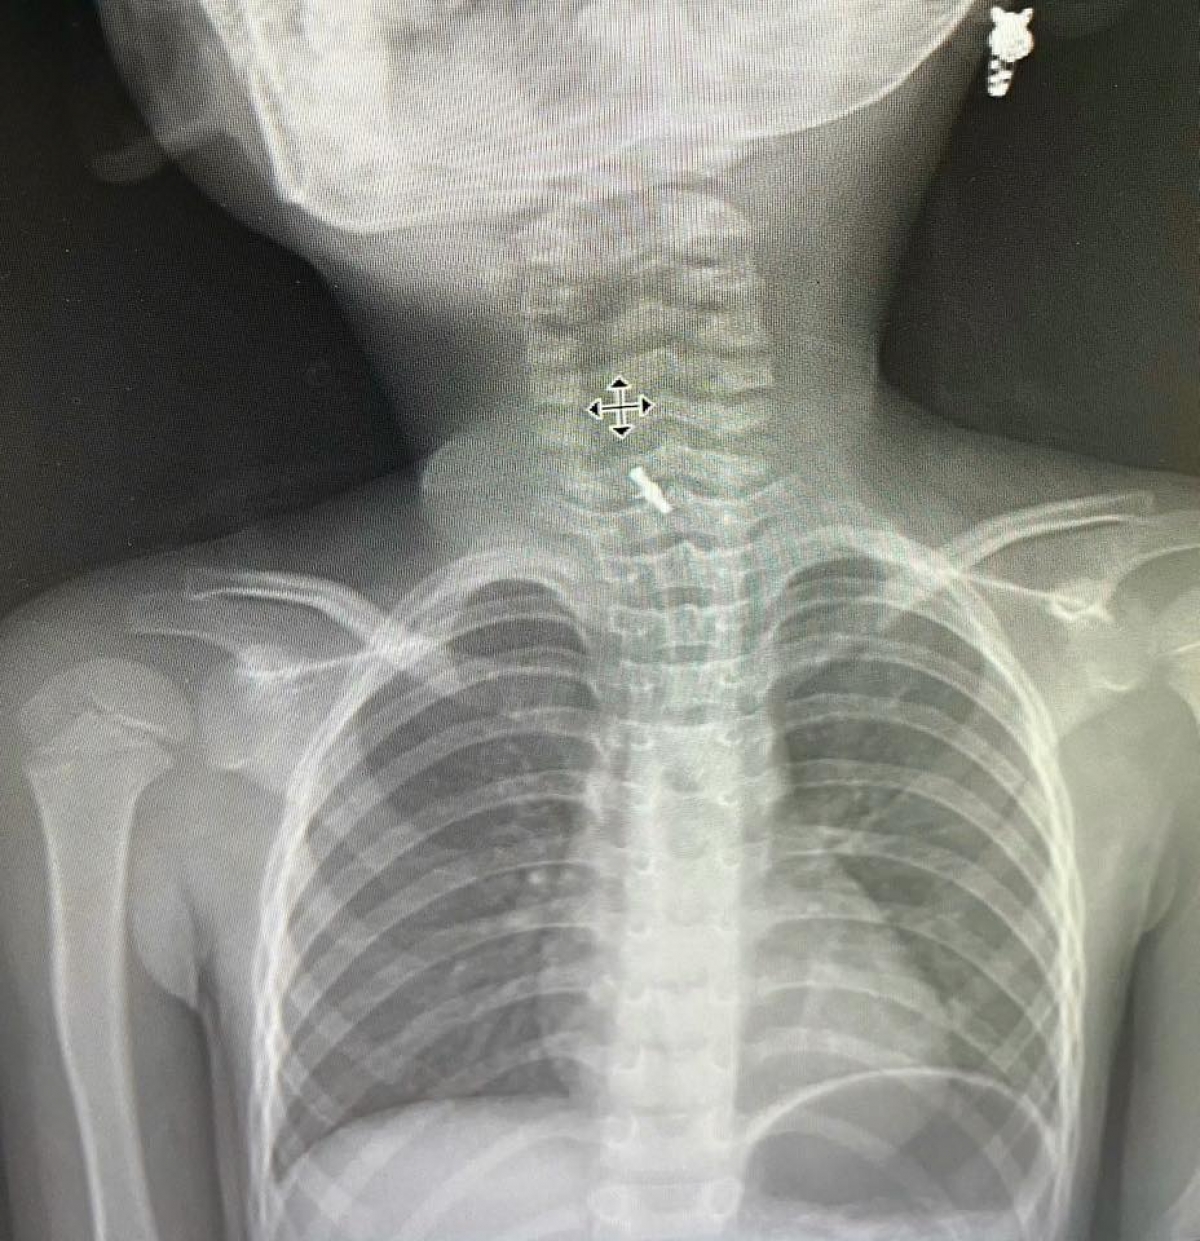

Cứu thành công bé 5 tuổi bị kẹt kẹp tóc trong thực quản

VOV1 - Bệnh viện Sản Nhi tỉnh Phú Thọ cho biết, đã cứu thành công một bé gái 5 tuổi bị hóc dị vật là một chiếc kẹp tóc mắc kẹt.

# Bệnh viện Sản Nhi tỉnh Phú Thọ cho biết, đã cứu thành công một bé gái 5 tuổi bị hóc dị vật là một chiếc kẹp tóc mắc kẹt. Trước đó, bệnh nhi 5 tuổi, ở xã Phú Mỹ, Phú Thọ được gia đình đưa vào viện vì đau rát họng. Gia đình cho biết khoảng một giờ trước đó, bé vô tình nuốt phải kẹp tóc khi đang chơi. Tại bệnh viện, sau khi gắp dị vật, hiện sức khỏe của bệnh nhi ổn định, đã ăn uống được thức ăn mềm và dự kiến sẽ xuất viện trong vài ngày tới.